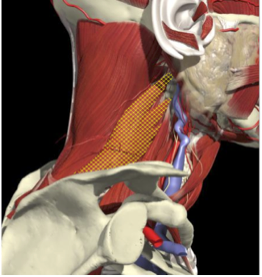

LATEROCOLLIS

Long muscles transversing spine

- Levator scapulae

- Scalenus Anterior/medius

- Semispinalis cervicis

- Longissimus cervicis

Biomechanical advantage

- Range - 37 degrees